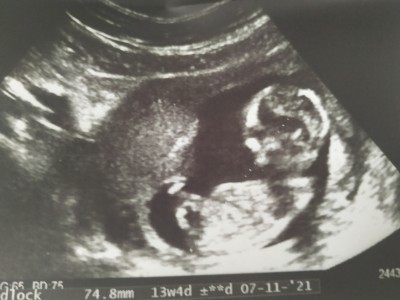

Benim için sizce kiz erkek bi tahmin yapabilir misiniz anneler bi türlü kendini göstermedi 14 haftalık

Kıza benzettim canım ☺

Erkek gibi geldi Allah gönlüne göre versin

Erkek gbi geldi annesi, hayırlı evlat olur insllah

Kız diyesim geldi ama içimden de erkek geçmedi değil, kararsız kaldım

Valla ilk klişe olucak sağlıklı olsun ama benimde gönlümden geçen kızım olması : )

Yarın gidicem bakalım ins öğrenebilirim